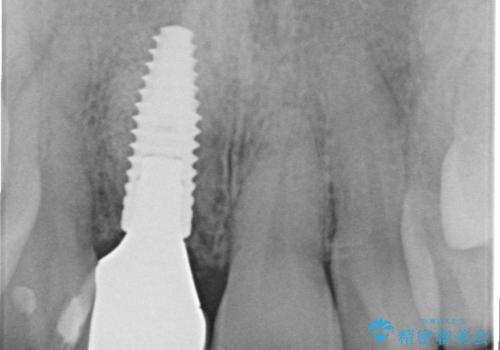

審美的・機能的に良好な位置に埋入するには、骨量が十分ではなかったため骨の造成を併用したインプラント埋入外科手術を行います。

前歯のインプラントを審美的に仕上げるには、インプラント周囲に十分な骨の量と厚みのある歯肉、そして埋入位置の精密な位置付けが重要です。